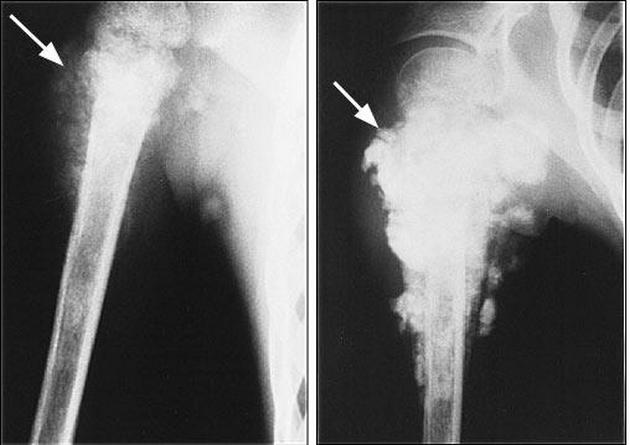

Рентгенологическая картина остеогенной саркомы кости - 98 фото